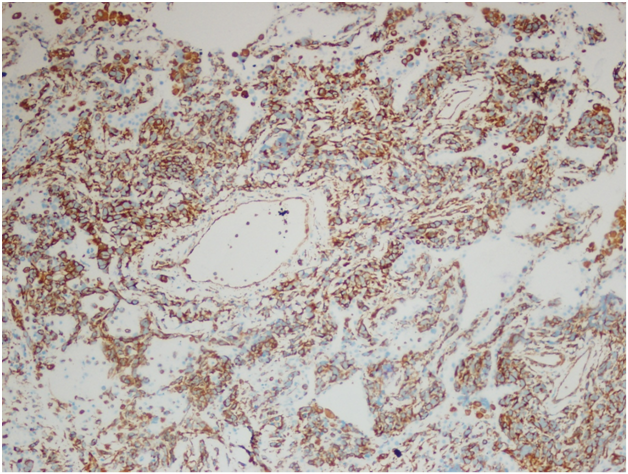

However, the wedge resection of the right lower lobe revealed angiosarcoma with lymphovascular invasion. This biopsy showed highly atypical and large malignant cells with increased mitoses (Figure 2A&2B). The immunohistochemical stains showed diffuse positivity for CD31, CD34, and vimentin (Figures 3A-3C). Stains for AE1/AE3 (Figure 3D), cam5.2, TTF-1, desmin, and OCT3/4 were negative. Along with the clinical history, a final diagnosis of angiosarcoma of the heart with metastases to the lungs was made.

Figure 3B Right lower lobe wedge resection. Immunohistochemical stain for CD34, 400x.